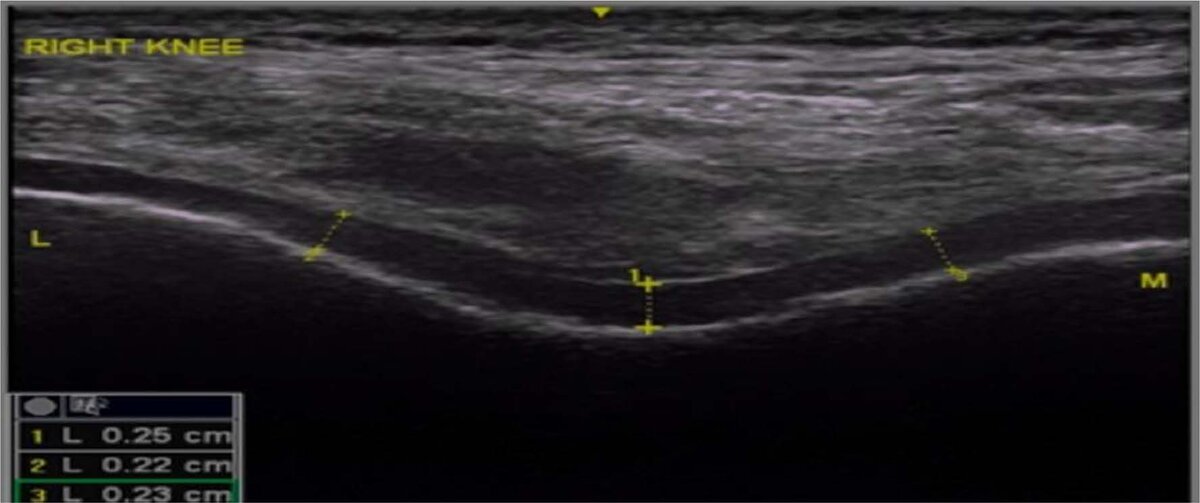

Рисунок 1 Ультразвуковое измерение толщины бедренного хряща на обоих коленях в трех различных местах (межмыщелковый, латеральный и медиальный)

Результаты показали, что в обеих группах наблюдались статистически значимые улучшения в показателях боли и функциональной активности, а также в толщине хряща уже на 2-й неделе лечения. Однако на 6-й неделе группа HILT + ET показала более выраженные улучшения по всем оценочным шкалам, включая уменьшение боли (VAS) и улучшение функциональной активности (WOMAC), а также значительное увеличение толщины хрящевой ткани. Это указывает на большую эффективность высокоинтенсивной лазерной терапии в комбинации с лечебной физкультурой по сравнению с плацебо-терапией.